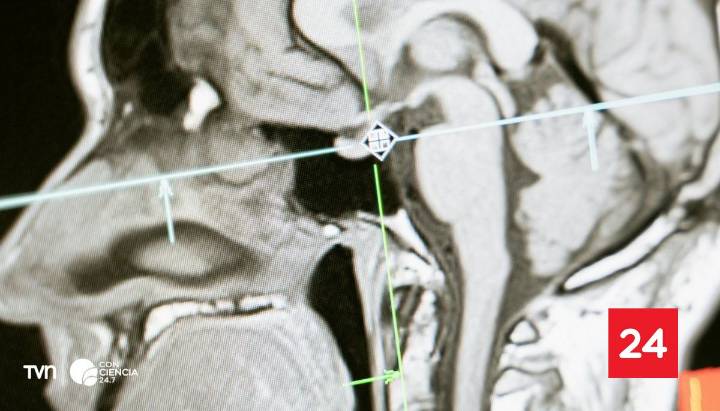

Un nuevo estudio publicado en Nature Communications identificó que el cerebro humano pasa por cinco grandes etapas a lo largo de la vida, definidas por cambios profundos en la conectividad neuronal . Según la investigación, dirigida por neurocientíficos de la Universidad de Cambridge , estas transiciones ocurren en cuatro momentos clave: a los 9, 32, 66 y 83 años .

El trabajo se basó en 3.802 resonancias cerebrales de personas entre 0 y 90 años, donde los investigadores analizaron las conexiones neuronales midiendo el movimi